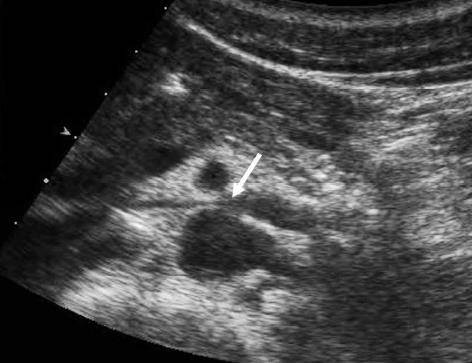

연합뉴스 보도에 따르면 호두까기증후군은 왼쪽 콩팥 정맥이 대동맥과 상장간동맥 사이에서 눌려 콩팥 안에 압력이 증가하면서 미세한 콩팥 조직과 혈관에 손상이 생기는 질환을 일컫는다.

증상으로는 왼쪽 콩팥 정맥의 압력이 올라가면서 콩팥 속의 작은 정맥이 터져 혈뇨가 발생하거나 단백뇨, 옆구리 통증 등의 증상이 나타난다.